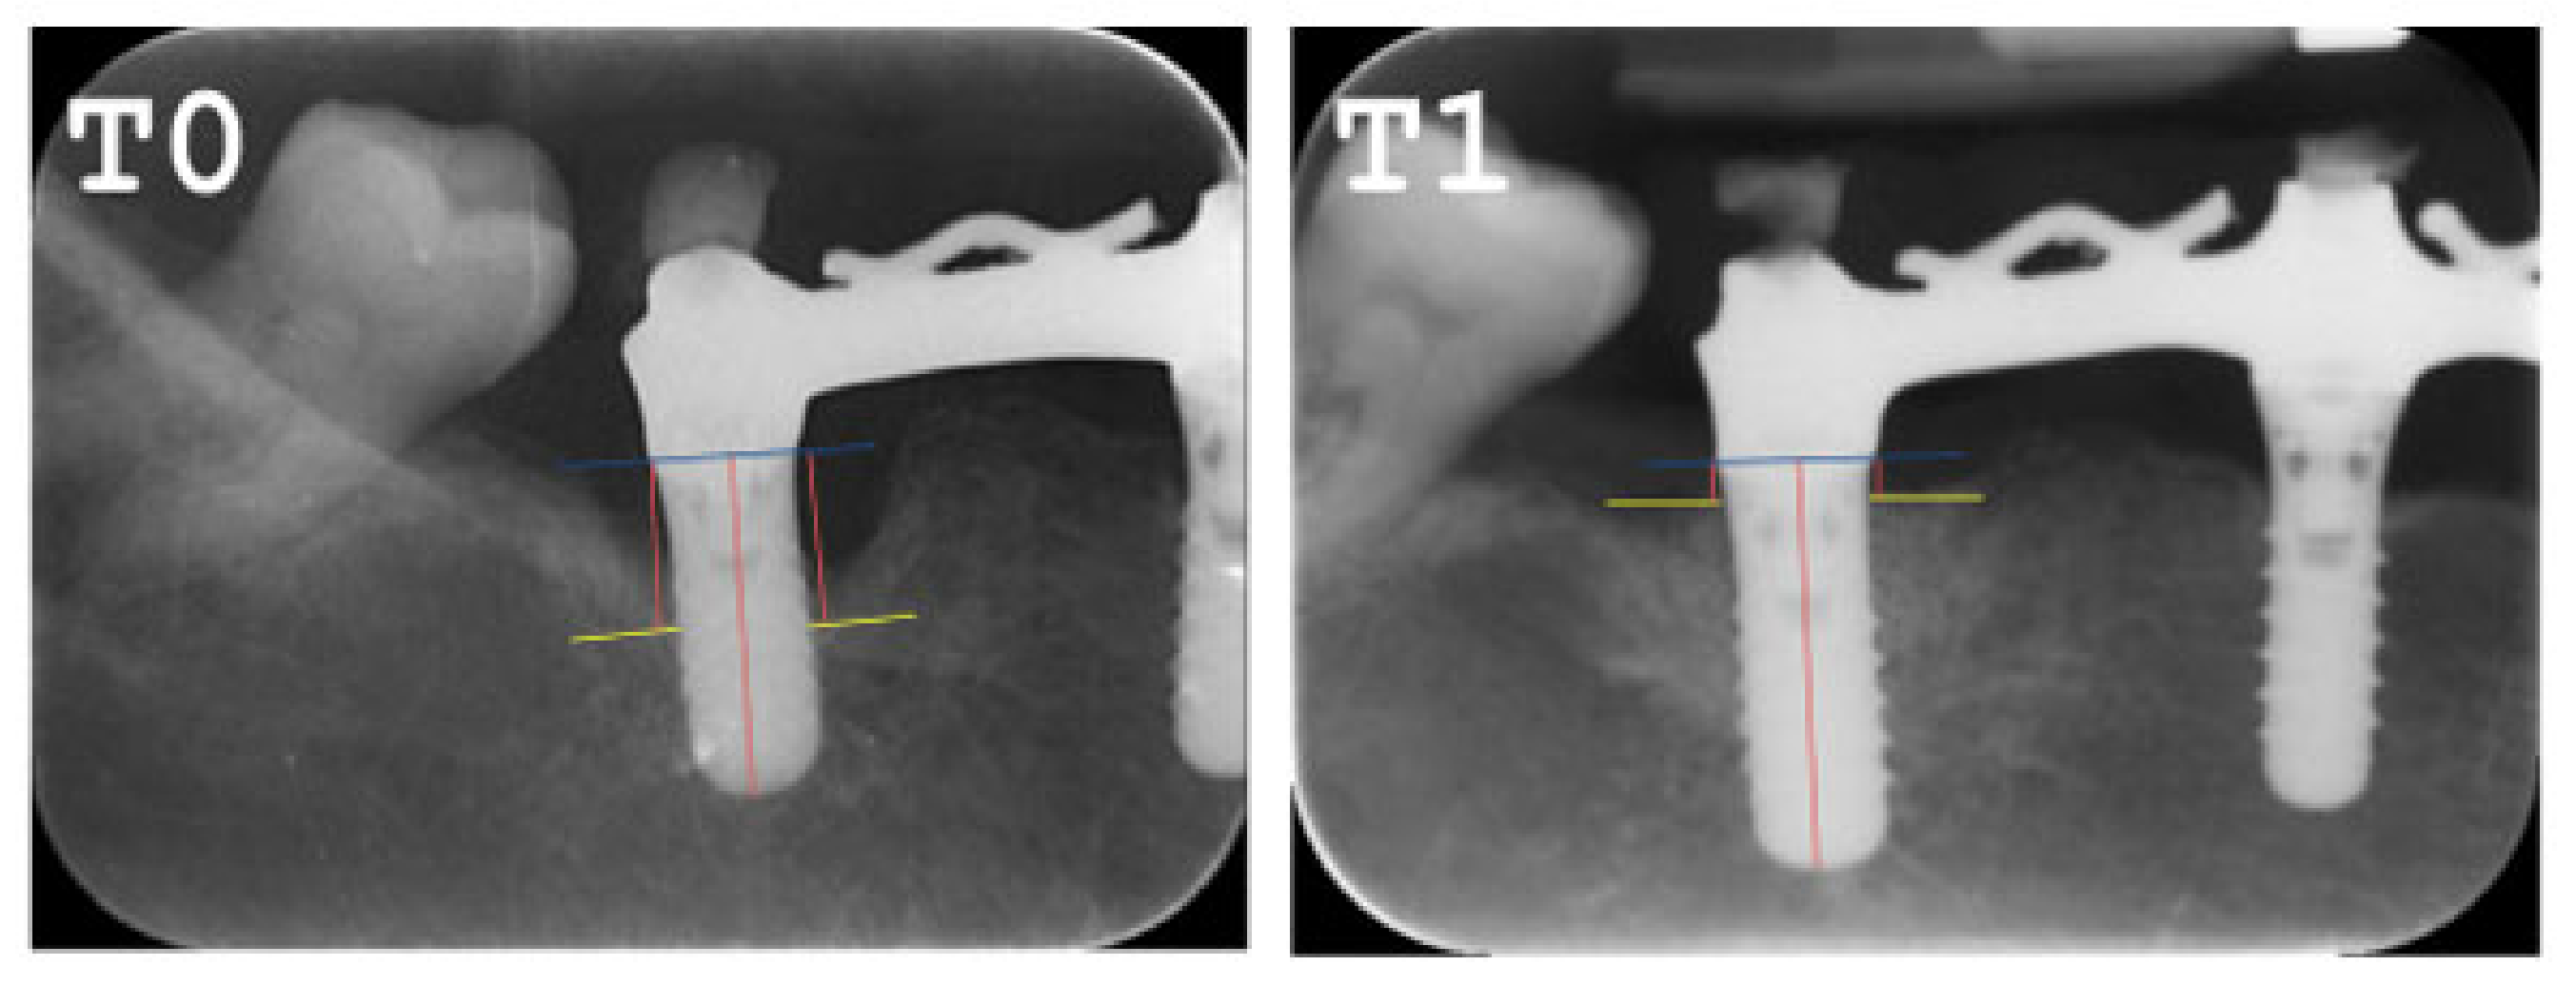

2.5. Radiographic Evaluation

- The MBL decreased from T0 to T1.

- A radiographic bone filling was obtained in most cases.